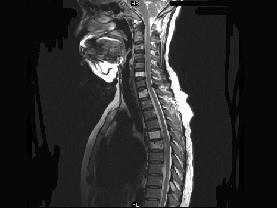

请结合提供图像,选择最佳选项 ( )A、退行性变B、脂肪瘤C、多发性骨转移D、骨血管瘤病E、骨结核

问题 请结合提供图像,选择最佳选项 ( )

选项 A、退行性变 B、脂肪瘤 C、多发性骨转移 D、骨血管瘤病 E、骨结核

答案 D